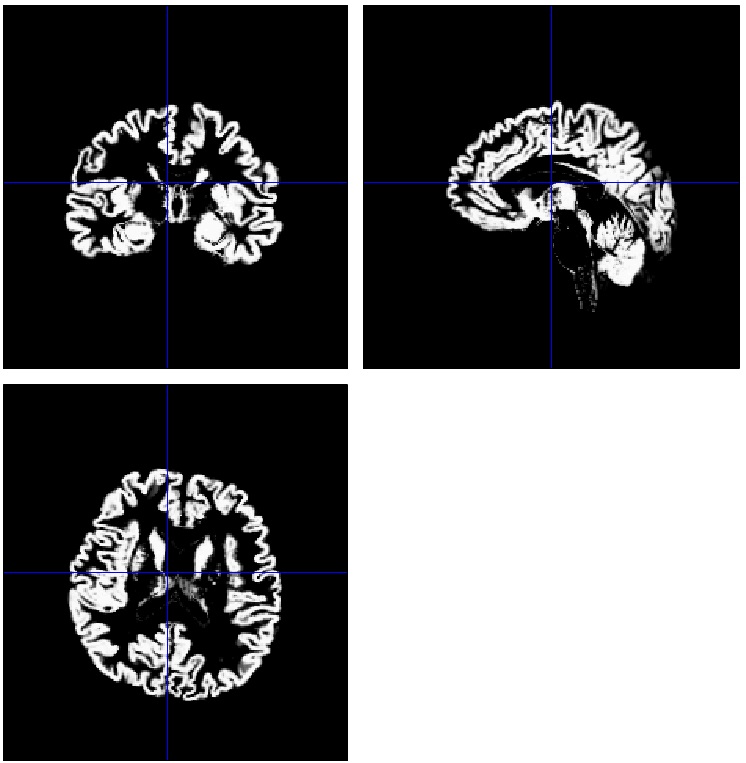

Segmentation

fMRIデータの前処理

PDF資料でSegmentationの方法を解説しています。